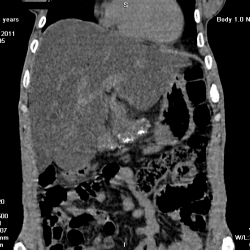

Мужчина 47 лет. Поступил по "скорой" с болями в правом подреберье-пояснице? "Скорая" поставила холецистит? В приемном отделении поставили: пиелонефрит? колика права? По ургентности УЗИ: образование...